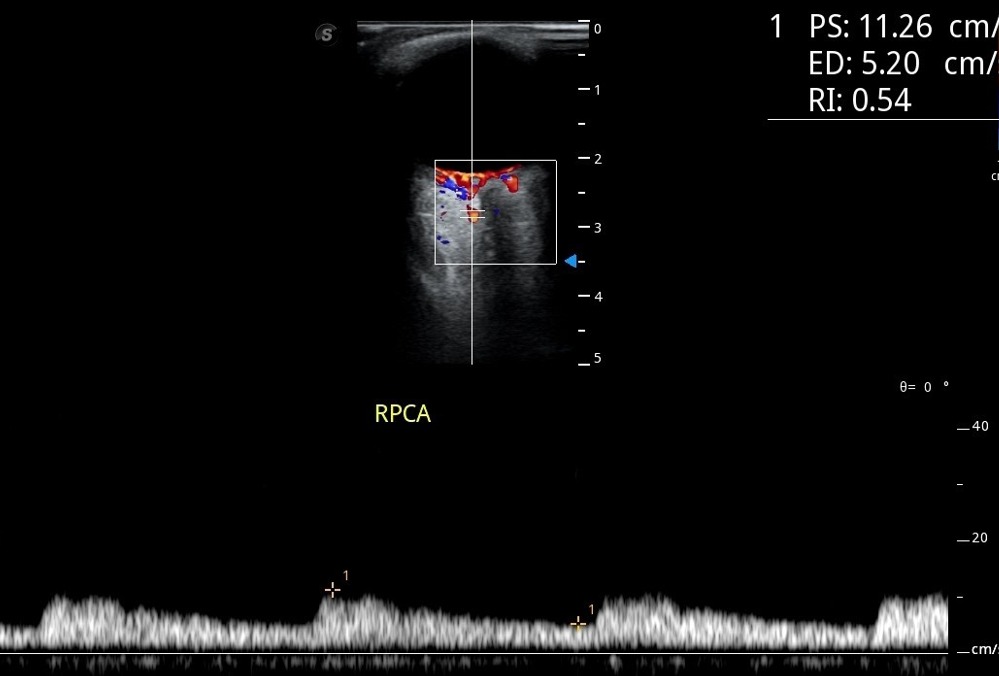

睫后短动脉主干在眼动脉第 2 段的不同处分出,解剖变异较大,但在视神经两侧至少各有 1 支短动脉, 位置较固定,彩色多普勒超声检查通常选择此部位取样。频谱显示睫状后短动脉呈斜三角形,也呈三峰两谷,峰谷之间差距不明显,峰速约 10 ~ 17cm/s(图 5 )。

图 5 睫状后短动脉多普勒频谱

图片来源:作者提供